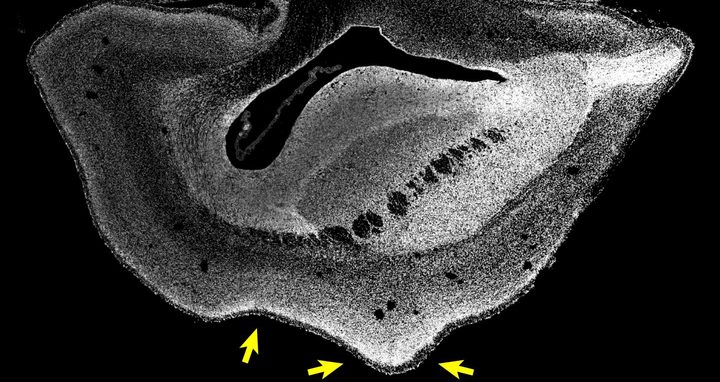

“De hecho, descubrimos que el neocórtex del cerebro del tití común se agranda y la superficie del cerebro se pliega. Su placa cortical también era más gruesa de lo normal”, refiere Michael Heide, el primer autor del estudio.

Con ello, los investigadores consiguen evidencia funcional de que ARHGAP11B causa una expansión de la corteza de los primates.